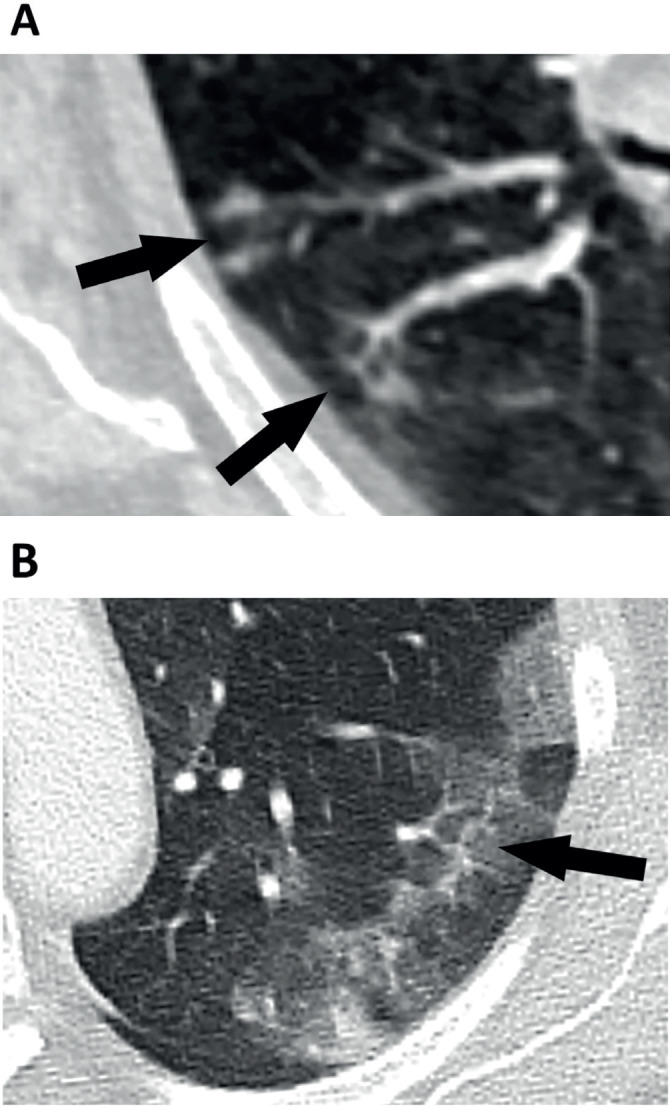

Results: Parenchymal lung damage was found in all subjects. However, airways inflammation was present in only 23% (9) and limited to small areas. Notably, vascular abnormalities were dominant and characterised by dilated peripheral pulmonary vessels supplying areas of lung damage in a gravity-dependent distribution bilaterally in 95% (38), basally in 90% (36), peripherally in 92.5% (37), and posteriorly in 90% (36). Macrothrombosis was demonstrated in 23% (7) of CTPAs. Wedge-shaped peripheral lung damage, resembling areas of pulmonary vascular congestion, were distinct in 53% (21) with or without visible macrothrombosis. Pleural effusions were seen in 28% (11). Notably, lung opacification distribution in 98% of the plain radiographs matched distribution on CT (39).